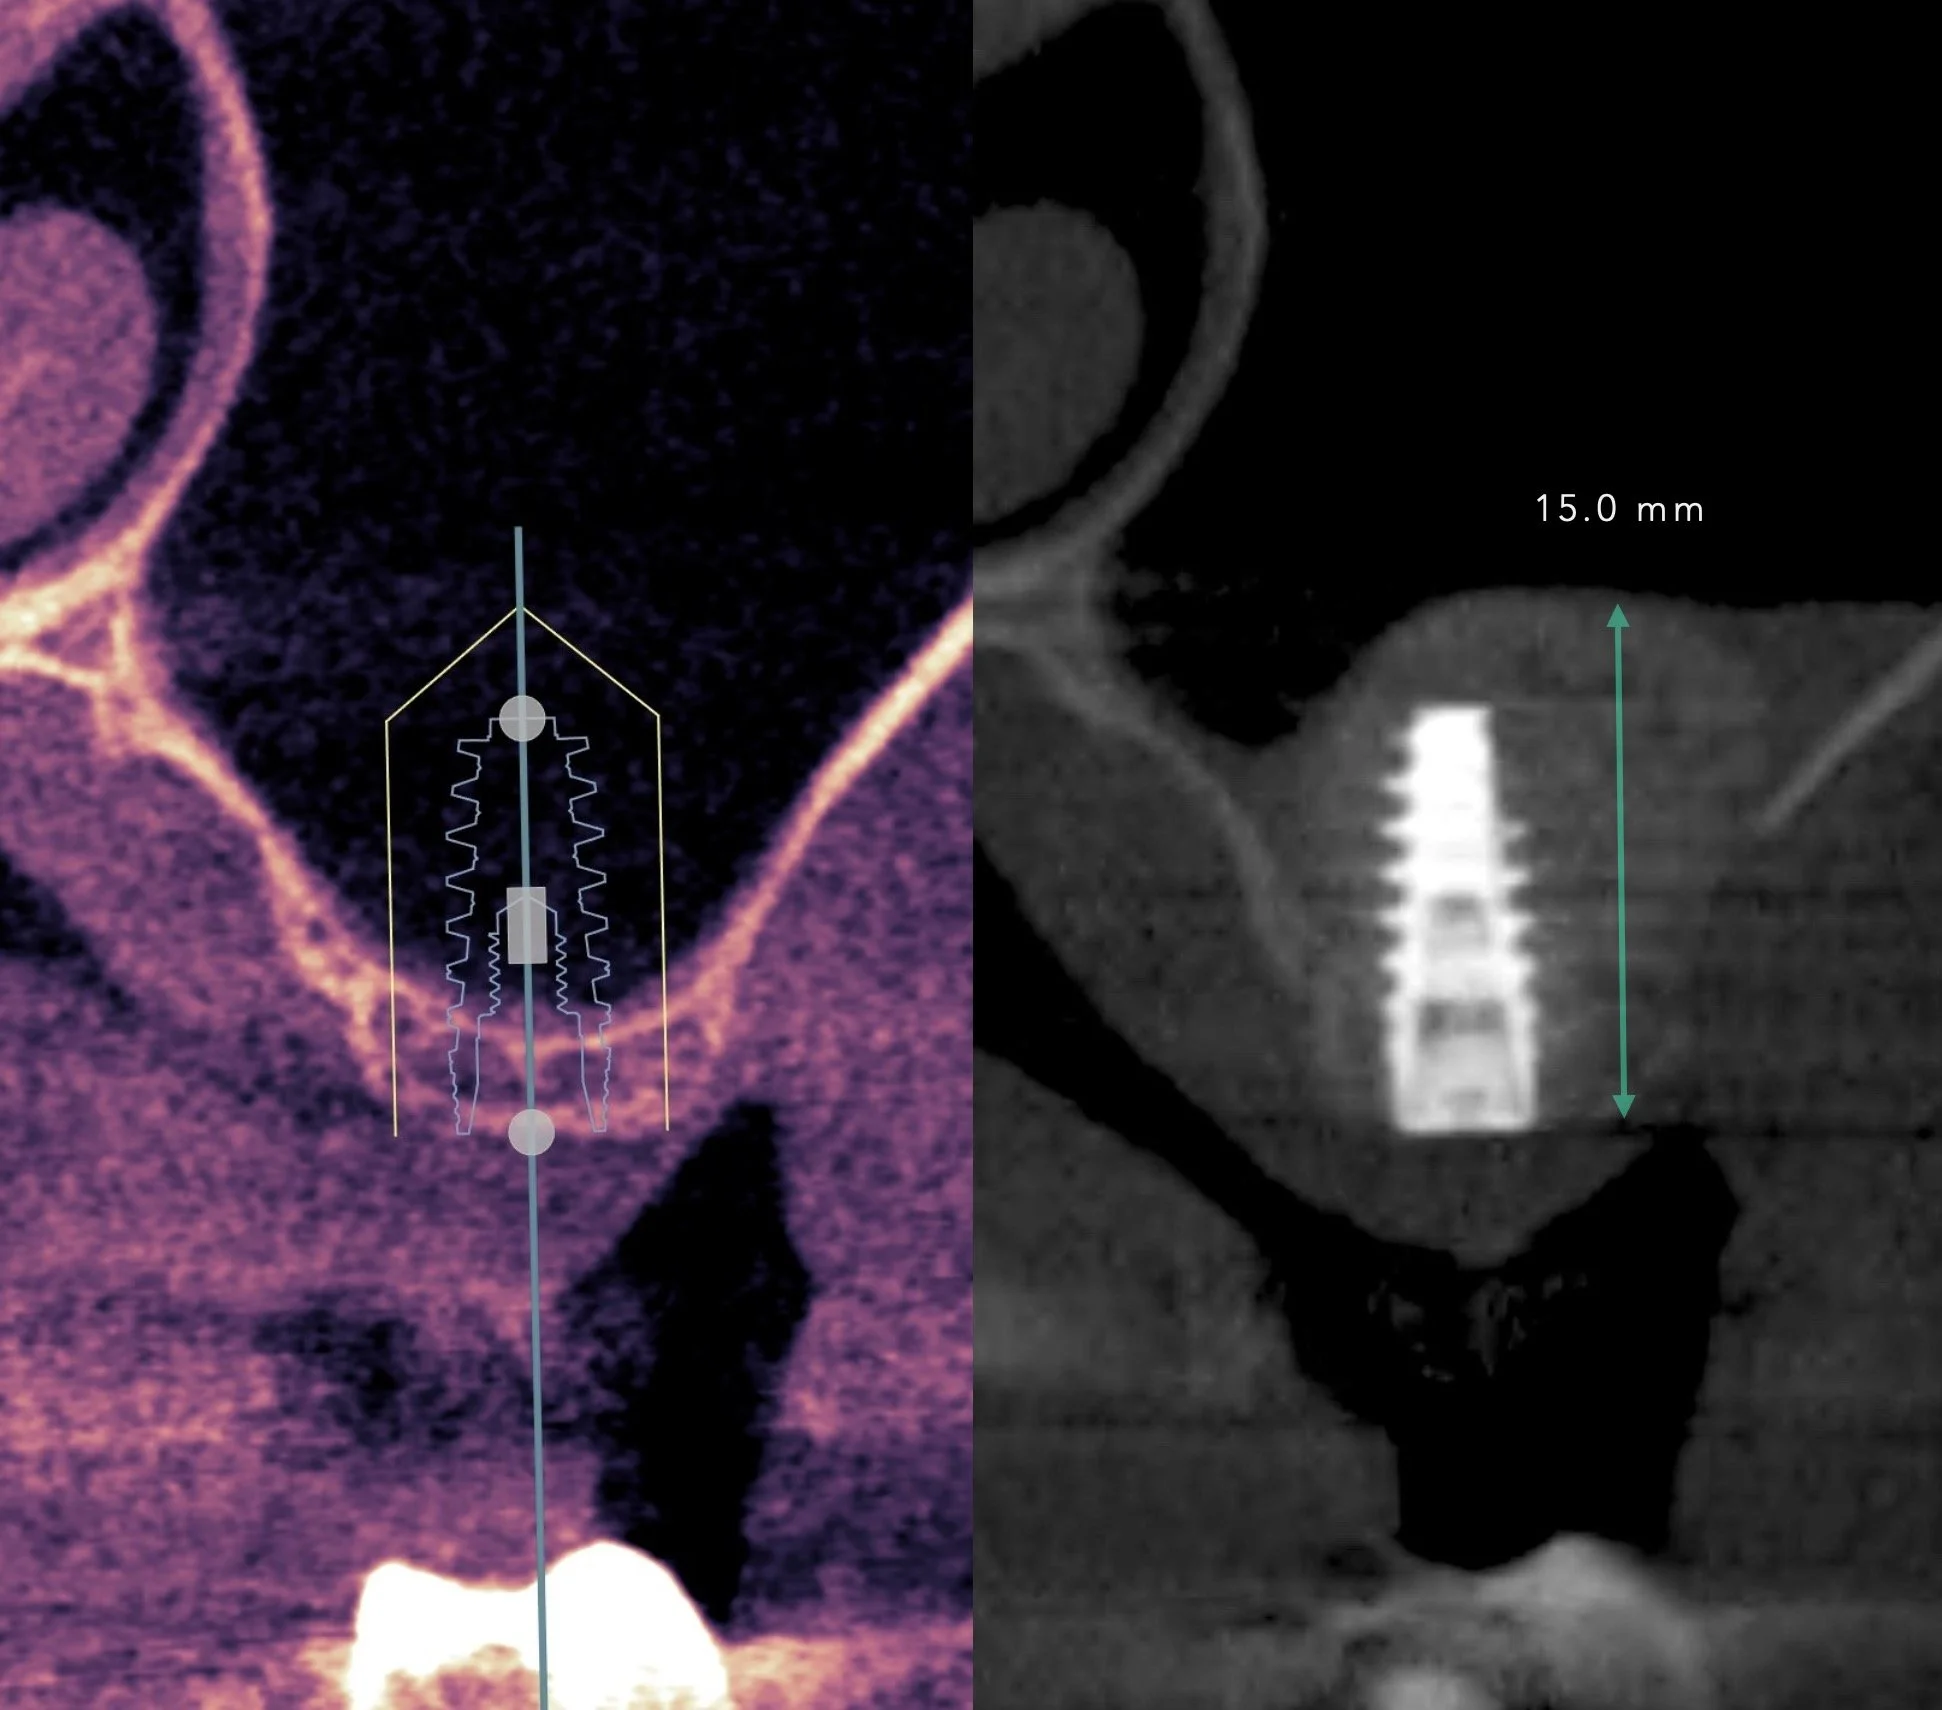

4 IMPLANTS + MAXILLARY SINUS LIFT

Porcelain, Zirconia, Titanium, and Resin.

Dr. Heldt, 2023. Newport Beach, California.

Maxillary sinus lift and 3 implants (NobelActive) were placed. After 8 months of healing and Invisalign treatment has been completed, Nobel Biocare custom abutments and layered eMax crowns finalized the case. Surgical + Restorative by Dr. Heldt. Invisalign planned by Dr. Liu.